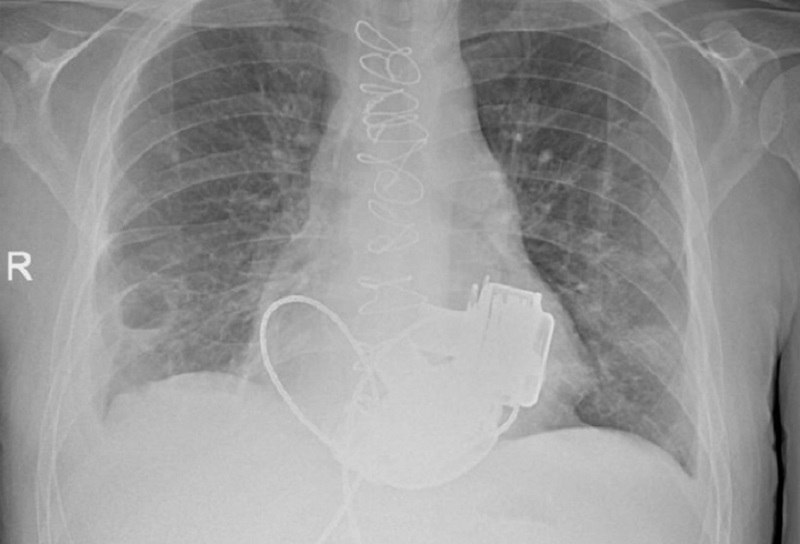

Пациента без пульса выпишут из больницы в Петербурге Уникальный пациент которому впервые в России имплантировали сразу два искусственных желудочка сердца готовится к выписке из Мариинской больницы в Санкт Петербурге В Мариинской больнице готовится к выписке уникальный пациент который с недавних пор живет без пульса В конце ноября 2025 года ему впервые в России имплантировали сразу два искусственных желудочка сердца левое и правое рассказали в комитете здравоохранения города Операцию провели в конце ноября 2025 года 36 летнего петербуржца экстренно госпитализировали с тяжелейшими диагнозами кардиомиопатией и терминальной сердечной недостаточностью По словам врачей функциональные показатели работы сердца были критическими и находились на уровне характерном для мертвого человека Решение о проведении сложнейшего вмешательства принял главный врач Мариинской больницы Игорь Реутский Операция длилась около четырех часов Самым трудным этапом стало согласование и синхронизация работы двух искусственных желудочков Сейчас состояние пациента стабилизировано Он проходит завершающий этап реабилитации и готовится к выписке Фото пресс служба комитета по здравоохранению Петербурга Подпишитесь на ivbg ru Ivbg в Max

В Санкт Петербурге врачи Мариинской больницы выписали домой пациента у которого пока нет пульса Он живет с механическим сердцем Уникальную операцию отцу двоих детей провели три месяца назад Больному впервые в России имплантировали сразу два искусственных желудочка Это временная мера перед трансплантацией У Антона Павлова теперь искусственное сердце которое работает от двух приборов на аккумуляторах Есть контроллер аппарат на который выводятся основные функции показывается количество оборотов в минуту пульсовой индекс мощность те параметры которые мы контролируем объяснила заведующая 1 м кардиологическим отделением СПб ГБУЗ Городская Мариинская больница Наталья Платонова Носить две сумки необходимо постоянно и не забывать заряжать аккумуляторы каждые 17 часов Но Антон уже привык Он понимает что это спасло ему жизнь Я рад что здоров что врачи меня спасли Спасибо им В принципе все хорошо Конечно риски были думал о рисках как все получится Но выбора не было Если бы не сделали операцию то я бы уже умер рассказал обладатель искусственного сердца Антон Павлов Антону всего 36 лет но в петербургскую Мариинскую больницу он поступил в терминальной стадии сердечной недостаточности с множеством осложнений Пациент с рецидивирующей тромбоэмболией У него постоянно образовывались тромбы которые стреляли в органы в легкие ему было трудно дышать у него развилась дыхательная недостаточность тяжелая на фоне тяжелой сердечной недостаточности говорит врач кардиолог СПб ГБУЗ Городская Мариинская больница Кристина Смелкова В такой ситуации спасти может только пересадка донорского сердца но провести трансплантацию оказалось невозможно из за противопоказаний Поэтому кардиохирурги решились заменить оба желудочка на механические Уникальная операция длилась четыре часа Пришлось отключить сердце пациента запустить искусственную систему кровообращения и имплантировать одновременно два механических насоса которые нужно было еще и правильно наладить Была проблема синхронизировать два искусственных левых желудочка которые у человека синхронизируются на уровне головного мозга вегетативной нервной системы А здесь две железки которые мы должны были сами искусственно садаптировать друг к другу поделился главный кардиохирург Санкт Петербурга академик РАН Геннадий Хубулава Операцию провели три месяца назад много времени понадобилось на восстановление Антону пришлось привыкать к гулу механических насосов которые теперь у него вместо сердца В принципе никаких ограничений у меня нет Я хожу я бы бегал если бы не сумки Чувствую себя прекрасно сказал Антон Ходить с сумками Антону придется недолго ведь через несколько месяцев он вернется в Мариинскую больницу чтобы получить донорское сердце Тогда и пульс к нему вернется